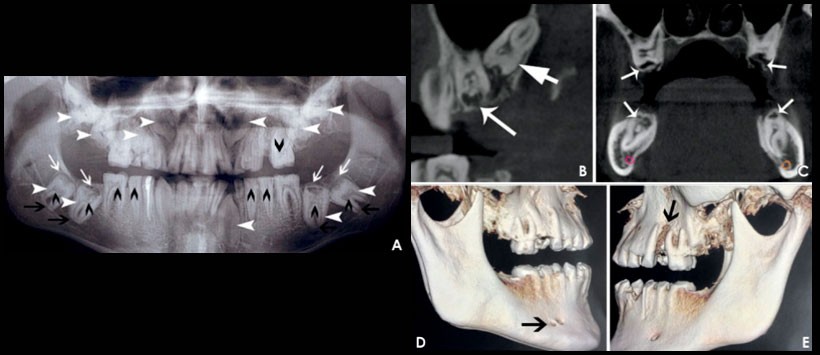

La radiografía panorámica y la tomografía computarizada con haz de cónico (CBCT) revelaron múltiples hallazgos. Todos los dientes se vieron afectados, especialmente los dientes posteriores (Fig. 2A). Se observaron múltiples calcificaciones en las cámaras pulpares de los dientes deciduos y permanente(Figuras 2A y B). La radiodensidad diferencial esperada entre la dentina y el esmalte estaba ausente (Fig. 2B). Los dientes impactados presentaron una completa formación de raíz, exhibiendo dilaceraciones y curvatura (Fig. 2A). Los folículos dentales alrededor de los dientes no erupcionados parecían ser hiperplásicos (Figuras 2A y B). Se observó una gran reabsorción de la corona con reemplazo parcial de la dentina reabsorbida por estructuras globulares calcificadas (Fig. 2C).